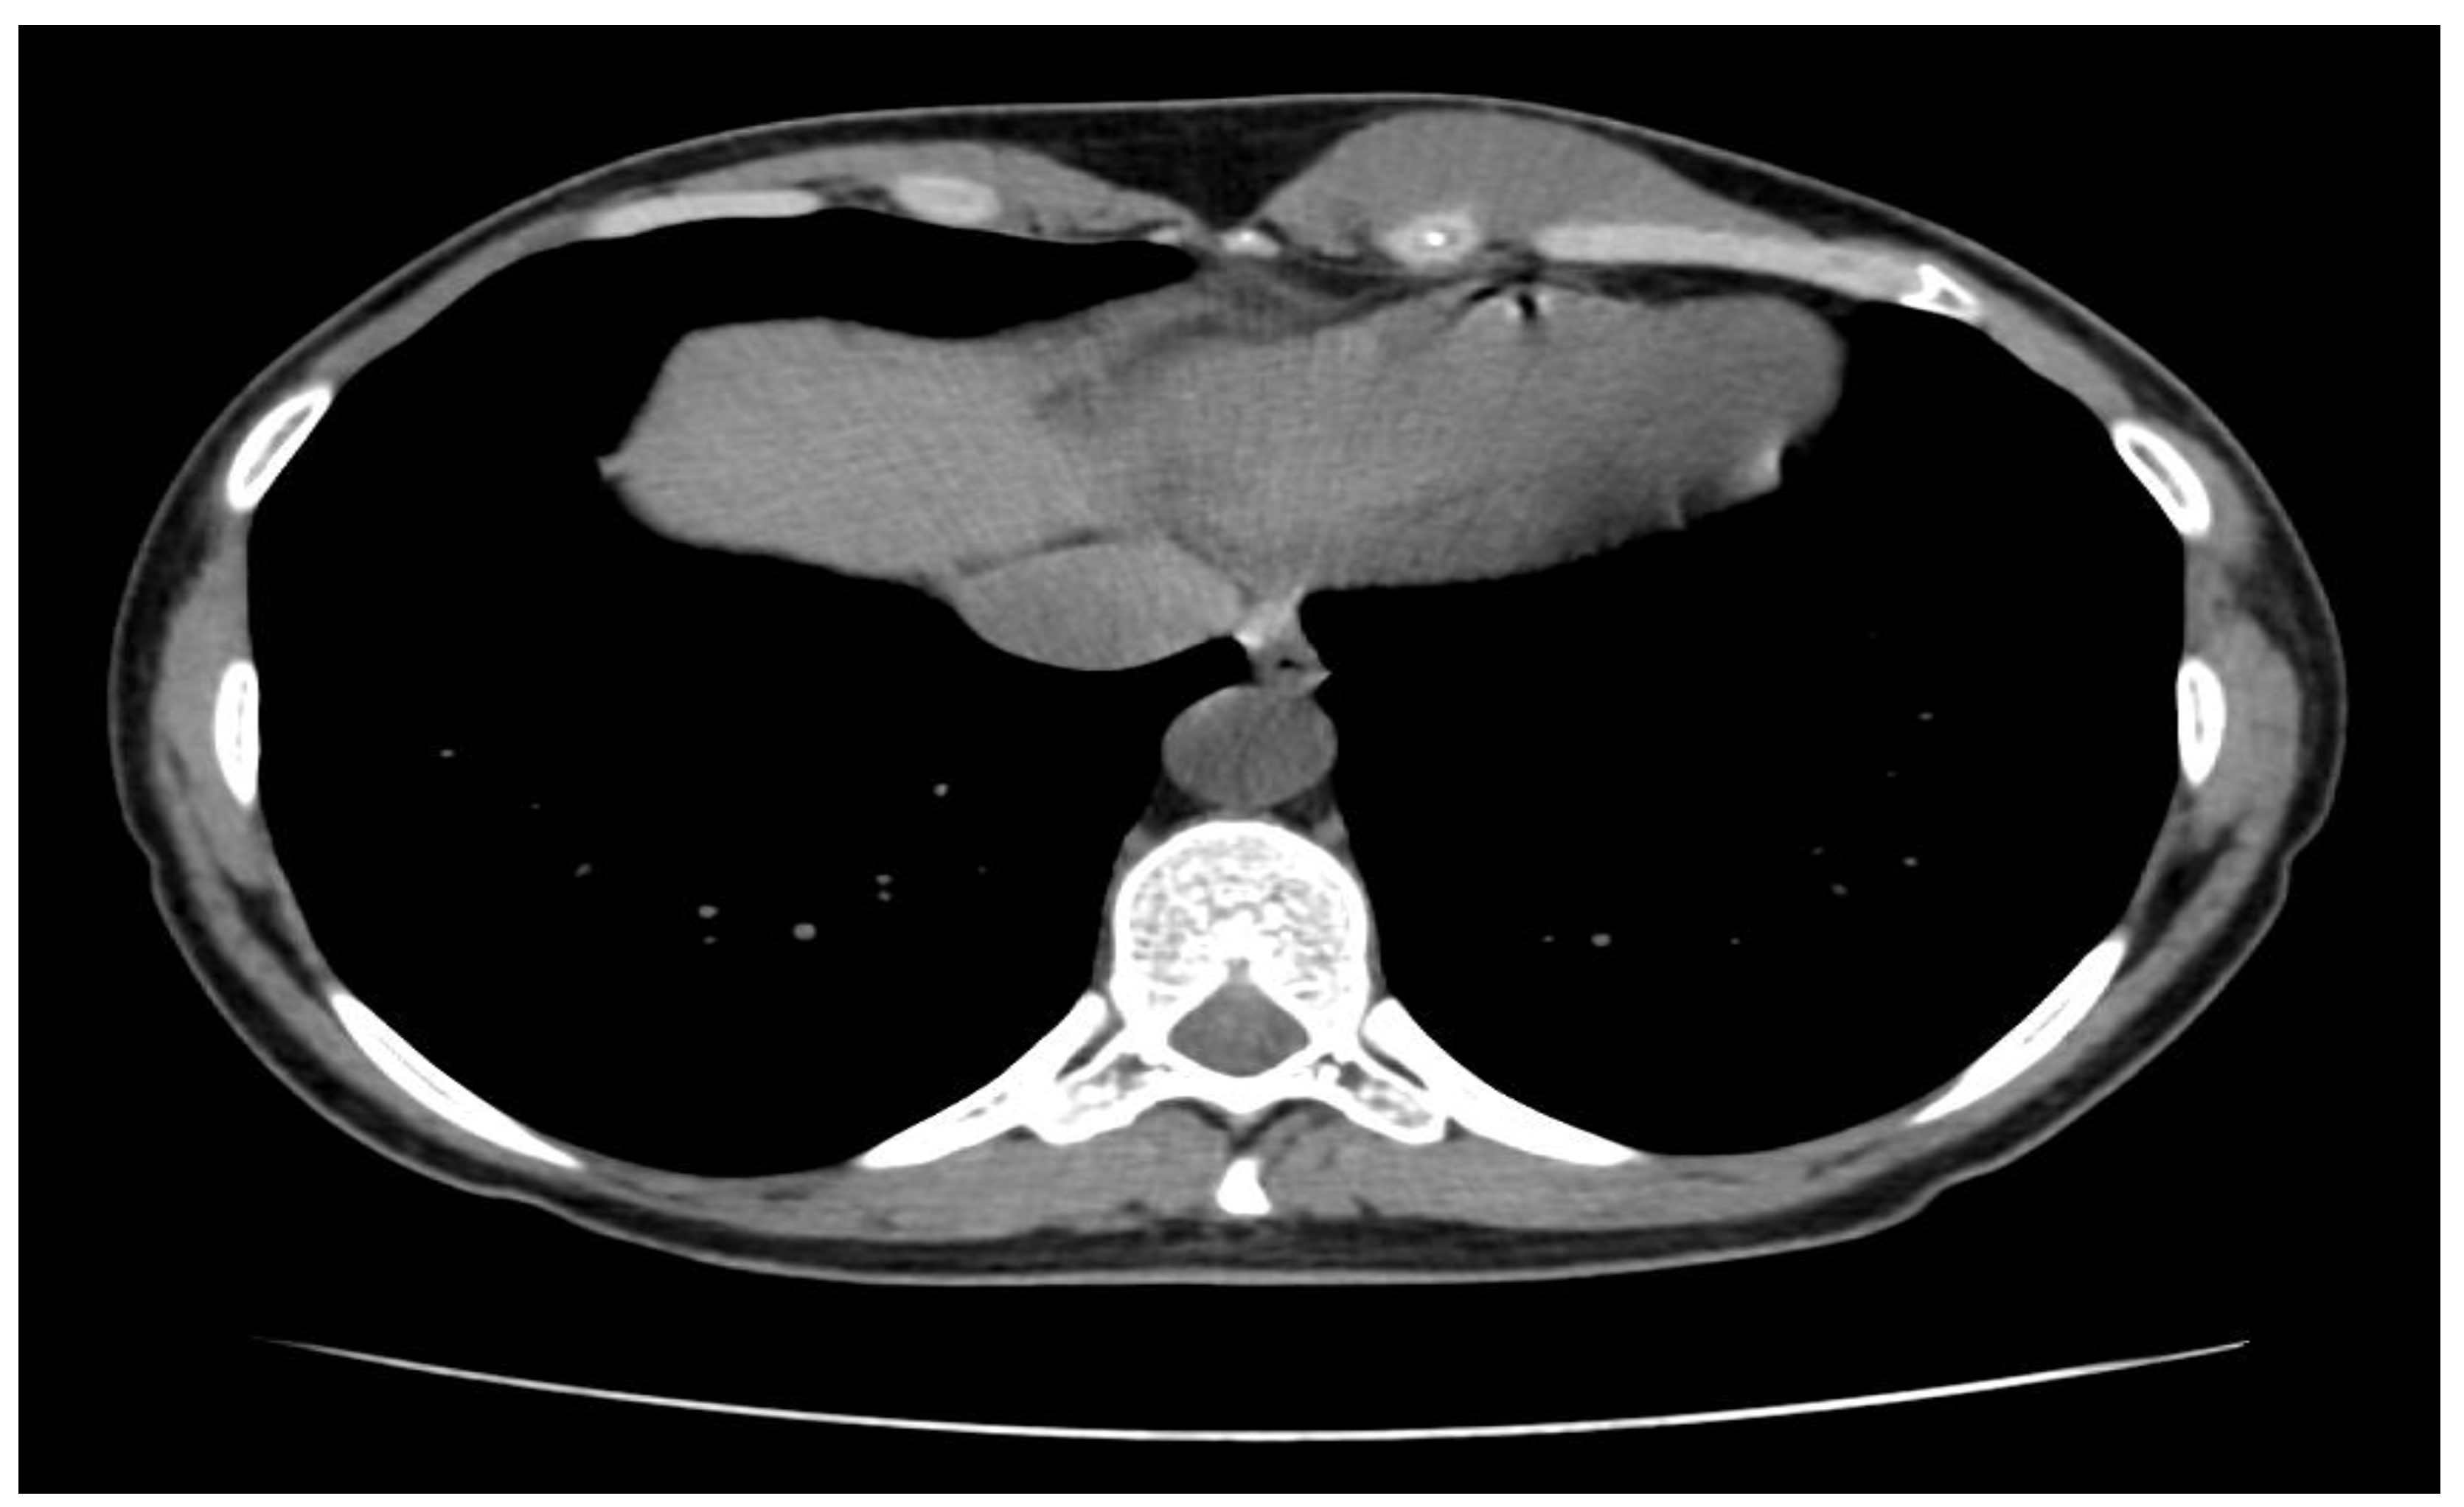

A soft-tissue ultrasound revealed a left paramedian parenchymatous mass measuring 4 × 2.7 cm, situated at the base of the hypochondrium, corresponding to the anterior XI-XII intercostal spaces. A contrast-enhanced thoraco-abdominal CT scan (Figure 1) further identified a well-defined, oval, intramuscular mass (22 × 48 × 55 mm, AP/LL/CC) within the proximal segment of the left rectus abdominis muscle, anterior to the VI-VII-VIII costal cartilages. There was no evidence of intra-abdominal or intrathoracic extension, adjacent tissue invasion, bone lysis, or suspicious adenopathies.

By September 2022, a CT scan revealed further tumor progression (36 × 76 × 75 mm, AP/LL/CC), with continued growth documented in January 2023 (47 × 74 × 91 mm). The tumor now featured intrathoracic and intra-abdominal extension, infiltrating the chondro-sternal cartilages of the VI and VII ribs, and contacting the homolateral V rib cartilage, without malignant transformation.

Figure 1. Thoraco-abdominal CT scan - desmoid tumor with intrathoracic localization.